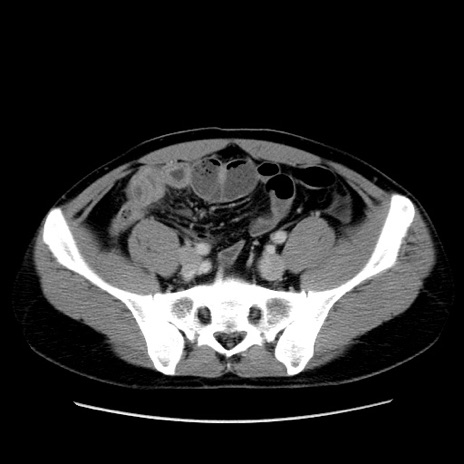

冠状断像

【症例】30歳代男性

【主訴】腹痛、嘔吐

【現病歴】昨晩から突然の腹痛あり、その後嘔吐、軟便も出現。腹痛が改善しないため救急搬送となる。2日前にしめ鯖の食事歴あり。

【身体所見】意識清明、苦悶様、BP 135/90mmHg、BT 35.7℃、腹部:平坦、やや硬、心窩部〜臍部に自発痛、圧痛あり、筋性防御+、反跳痛-

【データ】WBC 8100、CRP 0.57